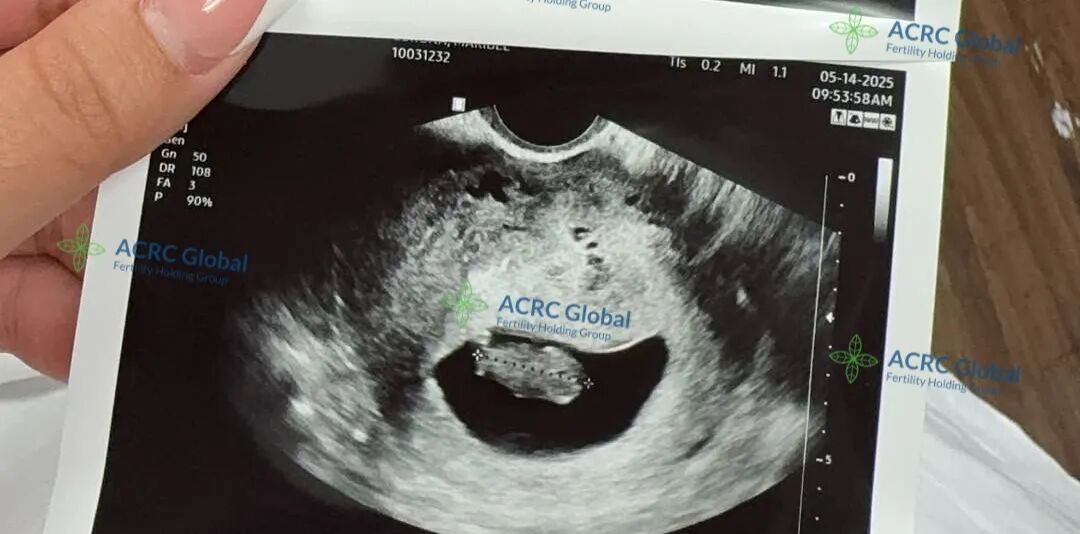

8周5天,胎心强劲

在顺利完成移植后,爱妈M迎来了首次B超检查,宝宝已经8周又5天,胎心强劲,达到176次/分钟,发育一切良好。感谢她的细心守护!

此次合作中,爱妈M匹配的是一位来自加州的单身准妈妈。这位准妈妈因为年龄因素更加珍惜这次成为母亲的机会,备孕之路走得格外用心与坚定。能够顺利进入孕期,是她多年来努力和等待的成果,也是一个梦想逐步成真的开始。